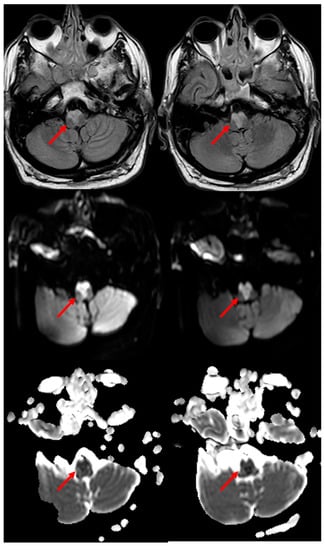

3.1. Medullary Infarction

3.2. Pontine Infarction